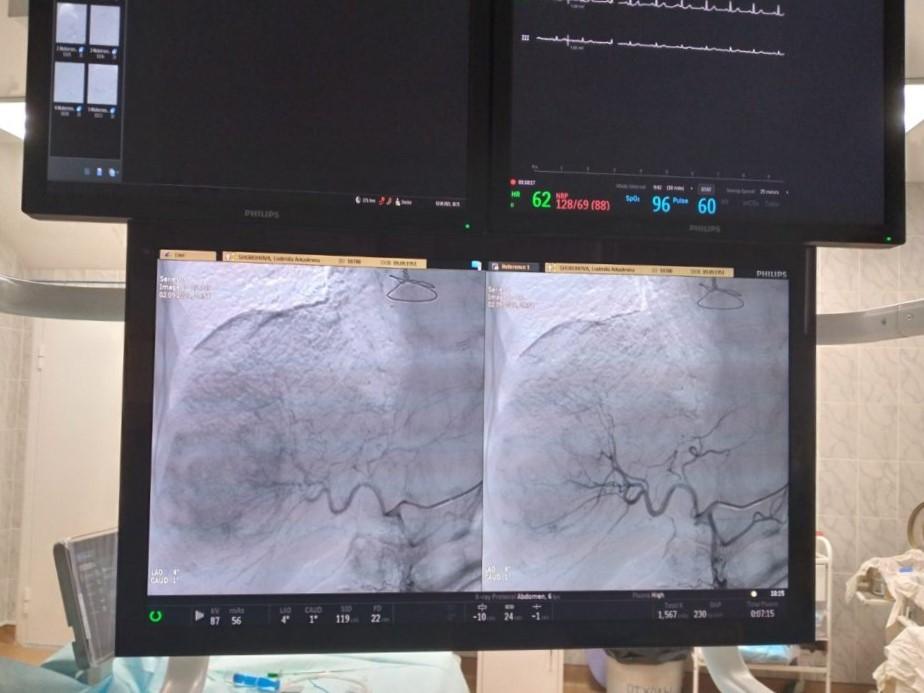

Еще совсем недавно для проведения этой процедуры южноуральцам приходилось, получив квоту, ехать в Санкт-Петербург, Москву или Екатеринбург. Теперь же, с июня этого года, необходимую помощь они могут получить в онкологическом отделении клиники Южно-Уральского государственного медицинского университета. В рамках федерального проекта «Борьба с онкологическими заболеваниями» в 2020 году получен новый ангиограф, весной нынешнего был закончен ремонт операционной и монтаж оборудования.

Селективная химиоэмболизация является сложным, но малотравматичным вмешательством, которое обычно проводится под местной анестезией интервенционными хирургами в рентген-операционной. «Для эндоваскулярной хирургии все самое интересное сейчас находится на стыке двух специальностей. Онкология — как раз такая отрасль медицины, где эндоваскулярная хирургия обязательна, в лечении этих пациентов используется все больше эндоваскулярных методов», — отмечает заведующий отделениями сосудистой хирургии и рентгенэндоваскулярной диагностики и лечения клиники ЮУГМУ Алексей Барышников, главный сосудистый хирург Челябинской области.